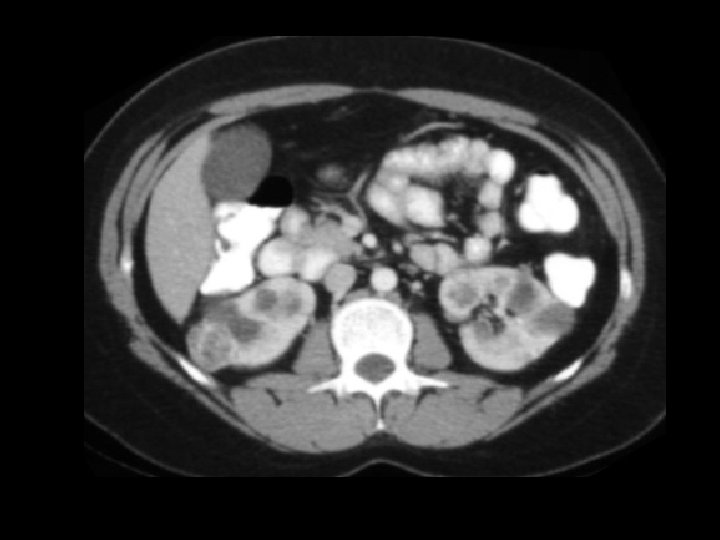

ADPKD • Findings: – Enlarged bilateral kidneys containing innumerable cysts – May also see hepatic cysts – Cysts complicated by hemorrhage or infection – NO increase risk of RCC • ddx: – NONE! – This is an Aunt Minnie!